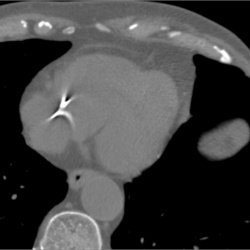

Мужчина 49 лет, состоит на туб. учете, к лечению не привержен, привержен к алкоголю. По поводу туб изменений в легких вопросов нет, непонятны изменения за тенью сердца (округлая тень с четкими...